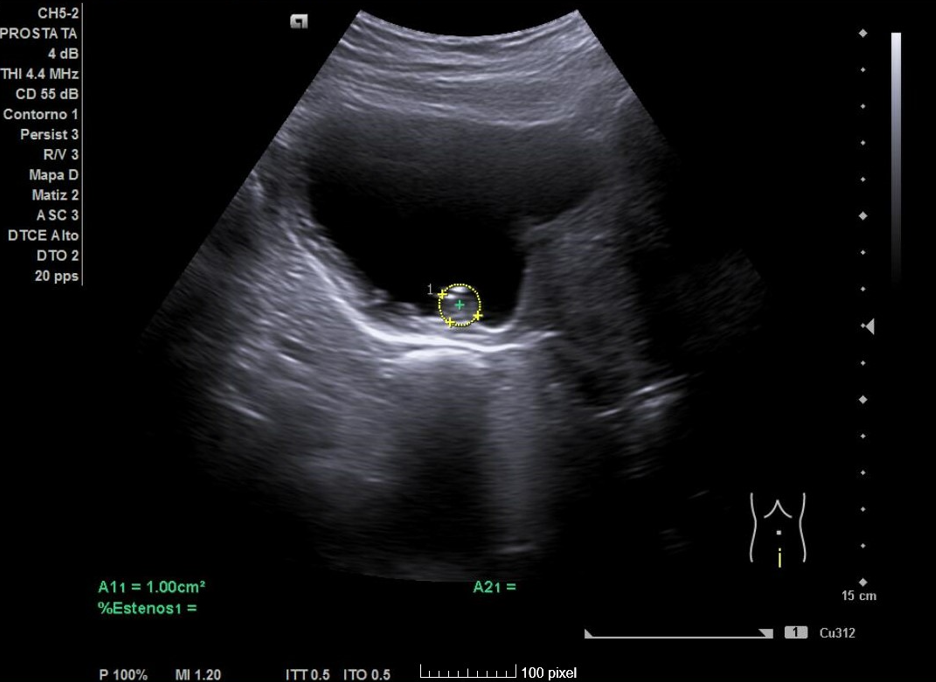

Primera ecografía: Riñón derecho de 9,6 cm, izquierdo de 9,5 cm, escoestructura y morfología normales. Vejiga con aumento de grosor de pared, residuo premiccional y posmiccional similares en torno a 350 cc (probable vejiga de lucha). Pólipo vesical a expensas de pared inferior izquierda de 18,5 x 8,7 mm. Jet ureteral bilateral conservado. Próstata de 110 cc. Se repite ecografía al mes: Pólipo vesical de 14 x 9,7 mm, próstata de 119 cc, vejiga con volumen premiccional 469 ml y posmiccional 400 ml.